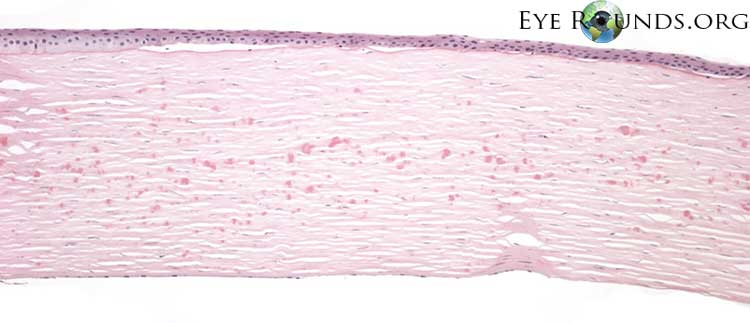

광학 현미경상,

과립성 호산성 침착물이 기질의 표층과 기질의 심부에 산재합니다.